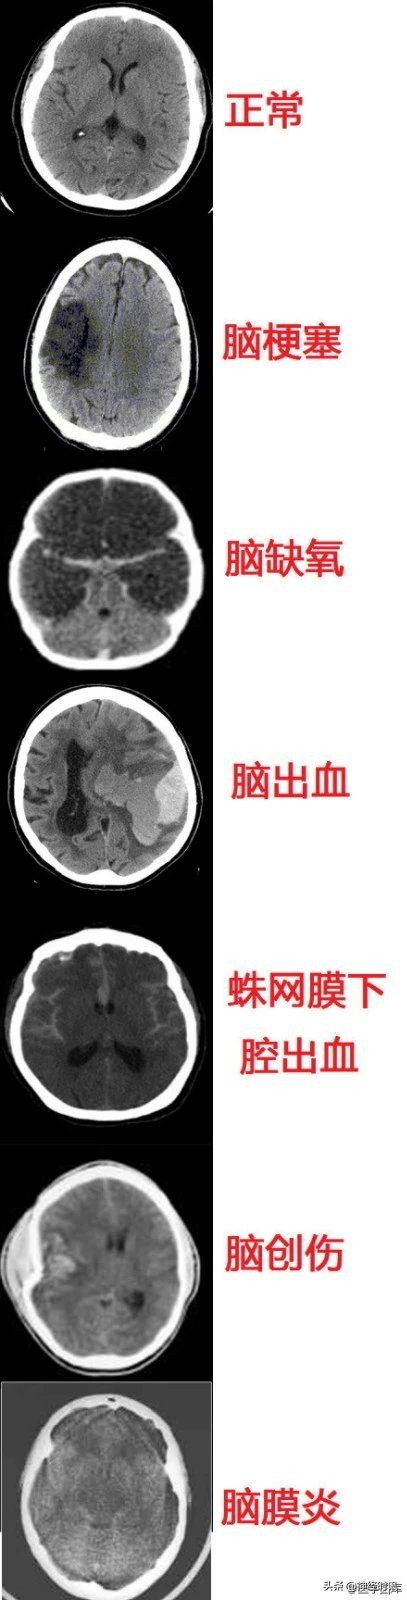

几种常见致死性脑病的CT表现

几种类型脑出血的CT表现